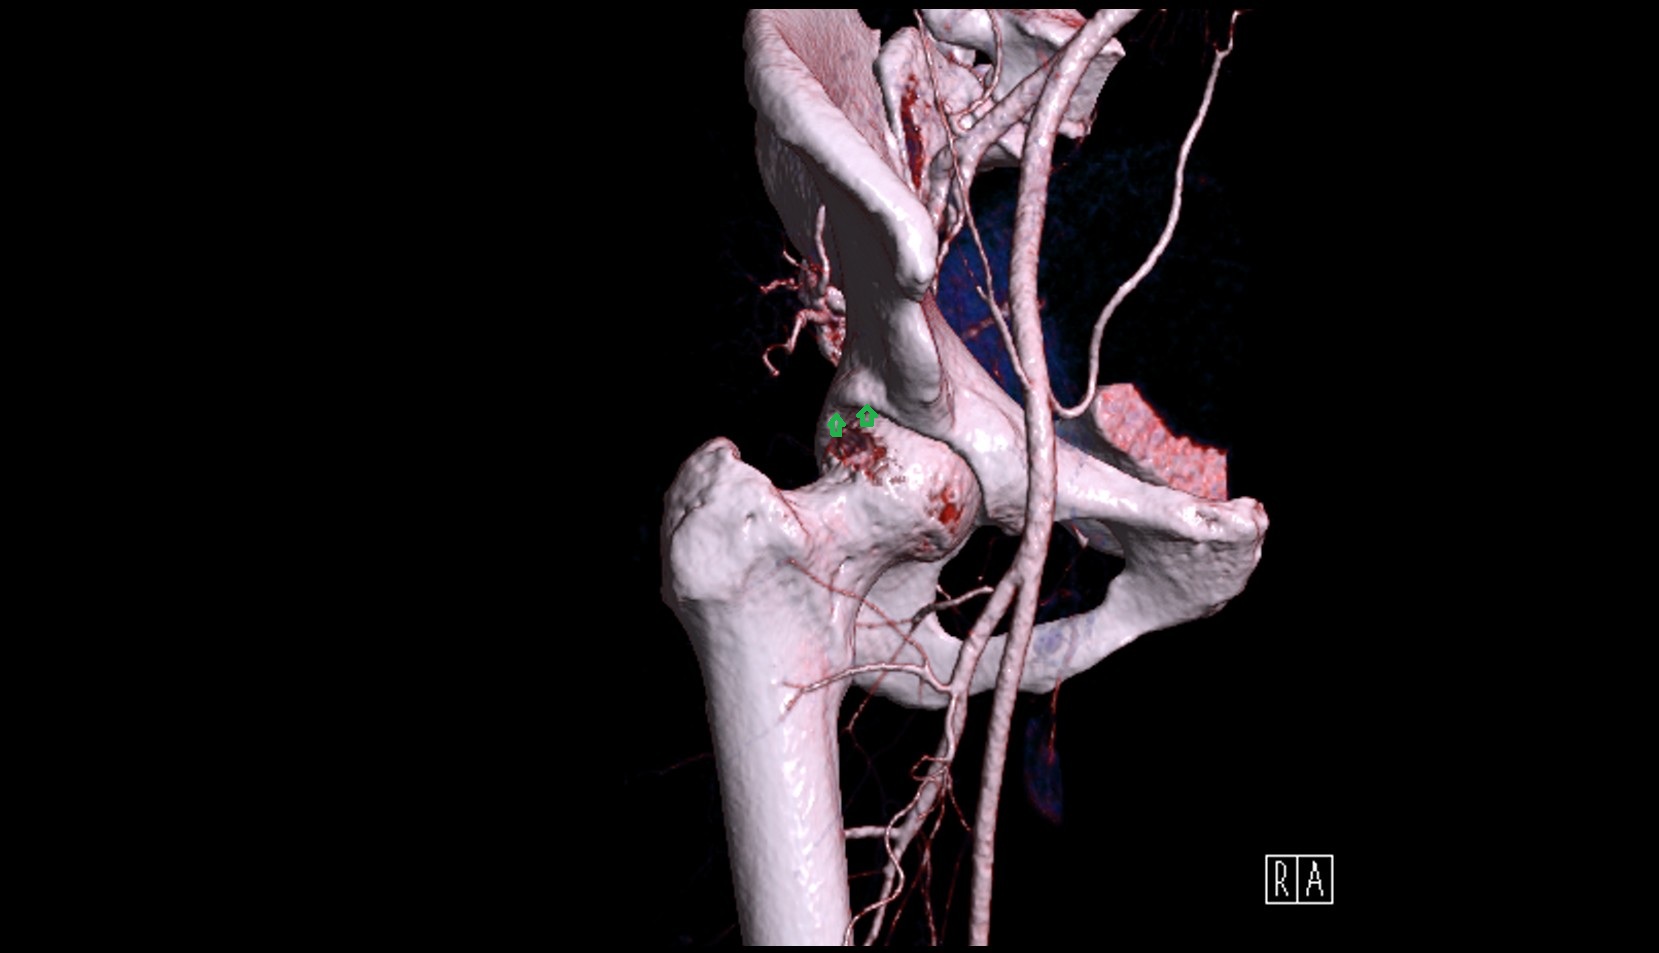

- Lateral circumflex femoral artery

- Deep femoral artery (profunda femoris)

- External iliac artery

- Femoral artery

- Internal iliac artery

- Medial circumflex femoral artery